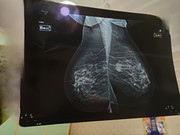

Buonasera dottor Catania, Le ho allegato immagini ecografia e mammografia 3d. Mi potrebbe dire qualcosa in più in attesa dell'esame bioptico?

REFERTO MAMMOGRAFIA 3D:

Densità mammaria di medio livello

Microcalcificazioni patologiche assenti

Si conferma in paraequatoriale esterna sinistra nodulo spiculato di 3 cm di diam max di natura eteroformativo.

In modesto ambito displasico fibronodulare si segnala altro irregolare nucleo densa in retroareolare destra.

Cute e capezzoli regolari con spazio chiaro perimammario normorappresentato.

Classificazione di rischio BIRADS 4c

reperto da sottoporre in prima istanza ad integrazione contrastografica (Mammografia CESM RM) ad accertare eventuale multifocalità.

Lei, vedendo le immagini allegate, è d'accordo coi referti?